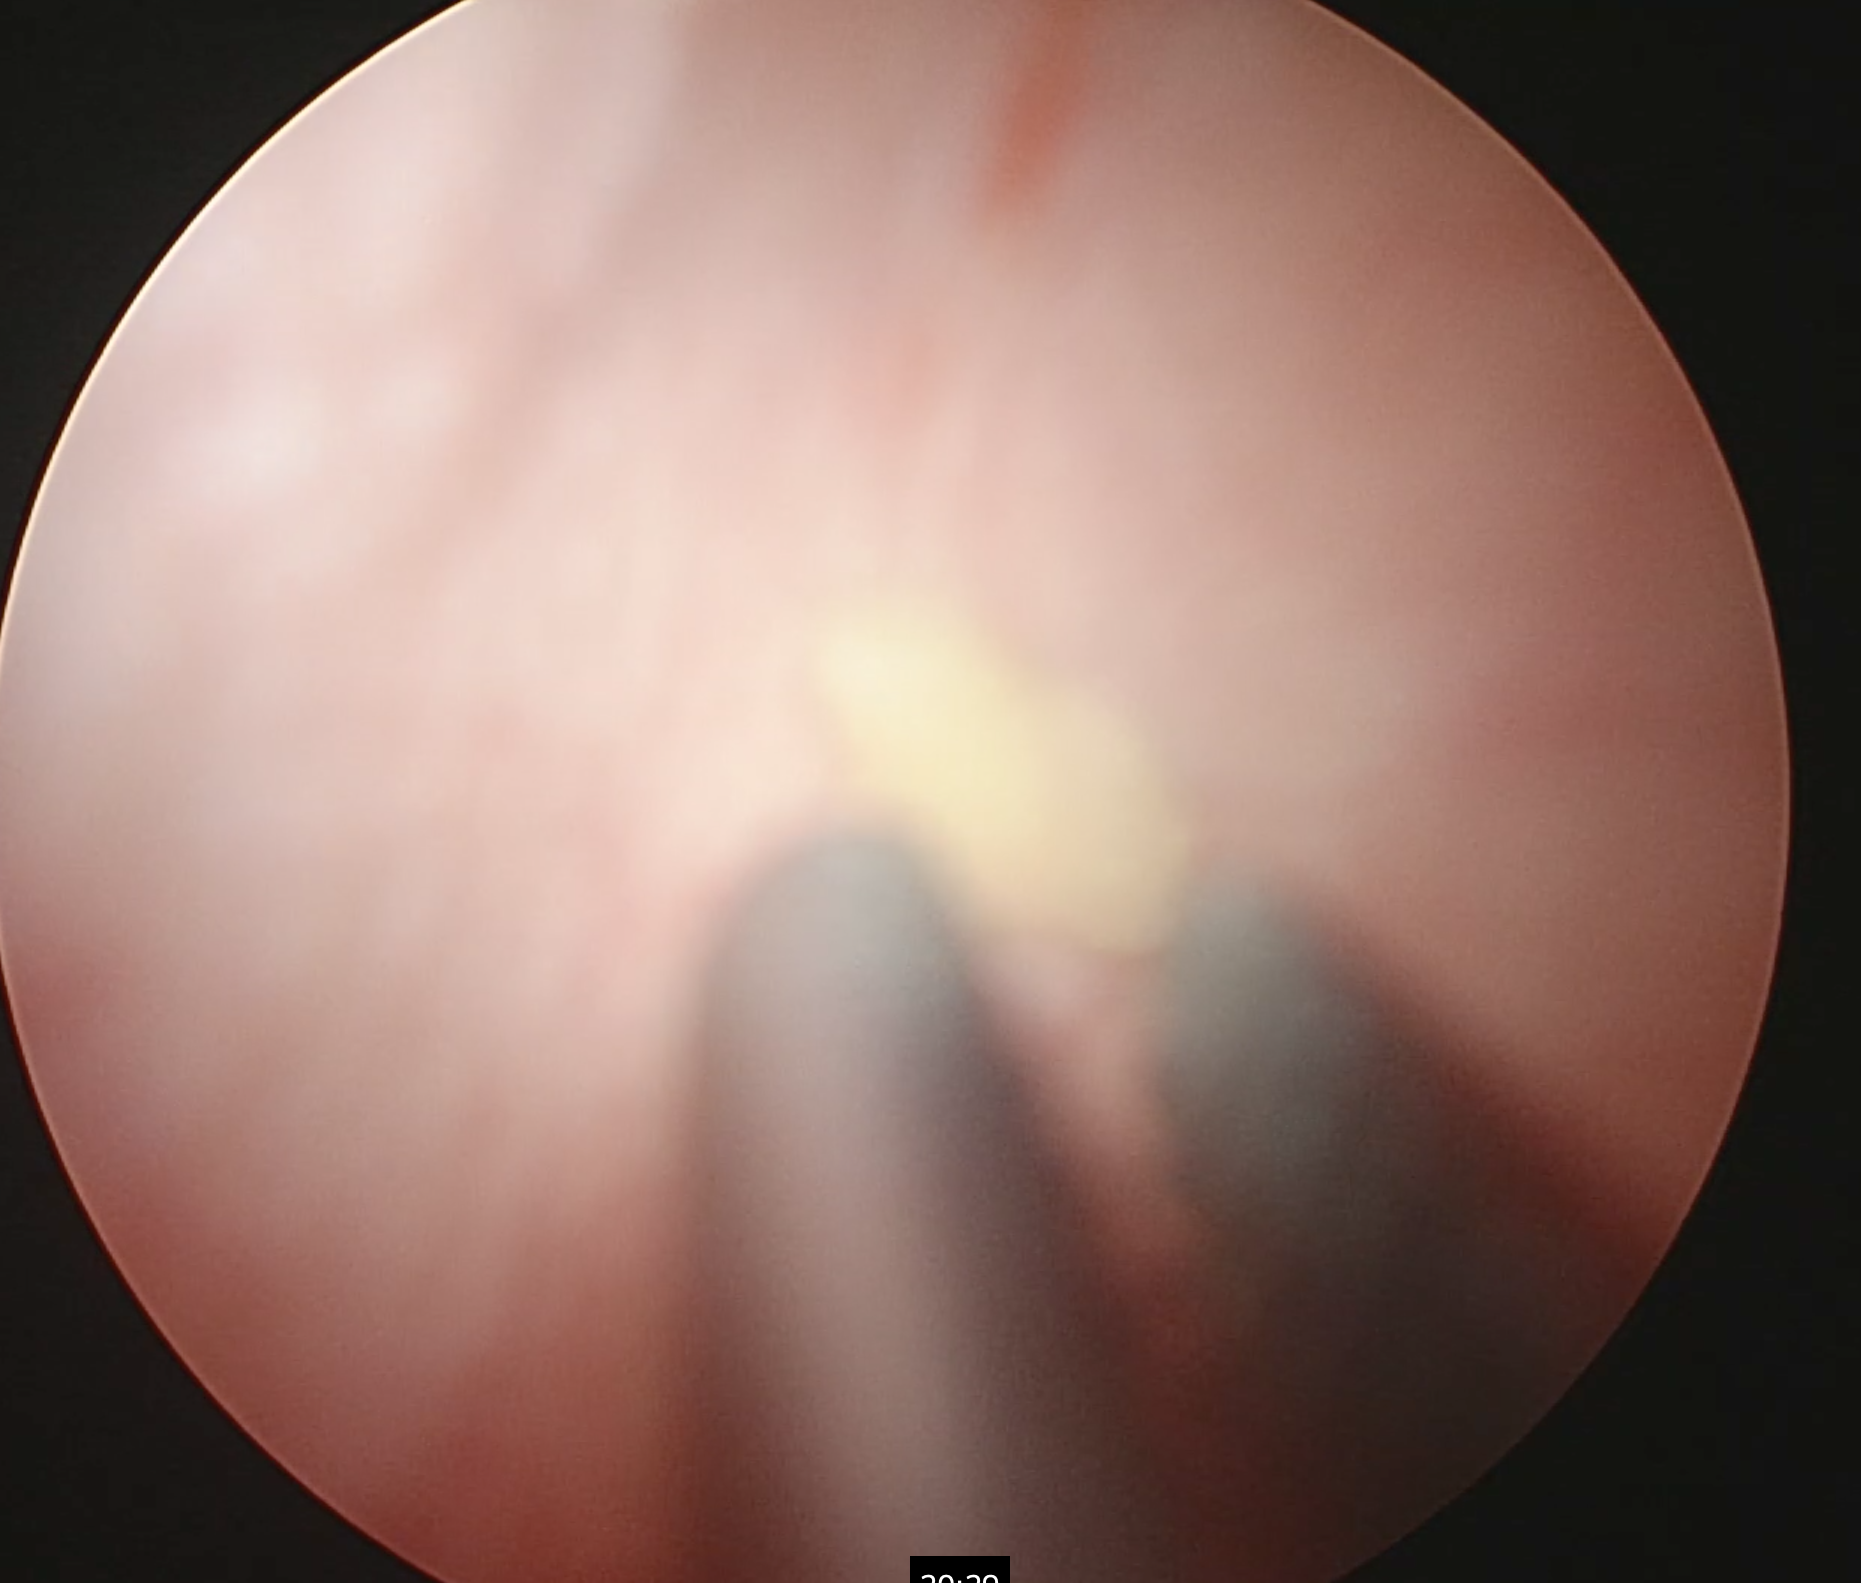

矢印は腹腔鏡カメラ越しに見た膀胱結石です。

専用器具を用いて結石を摘出しています。